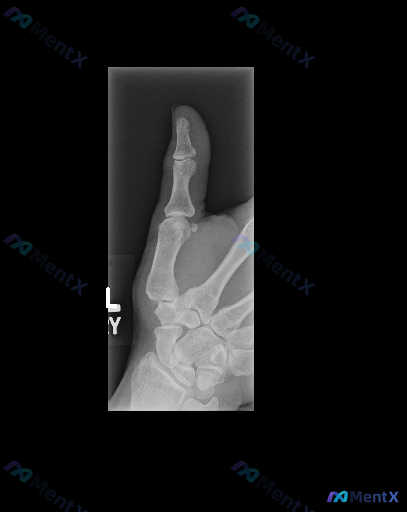

整理到一份左手拇指及腕部的影像资料,觉得挺有讨论价值的。 先看X光报告的“表面结论”: - 投照体位是左手拇指及腕关节斜位 - 拇指近远节指骨、第一掌骨、舟状骨等腕骨骨皮质连续,未见明确透亮骨折线 - 关节对位、间隙基本正常,无明显脱位或骨质增生 - 软组织也未见明显异常高密度或肿胀 但这份资料同时...